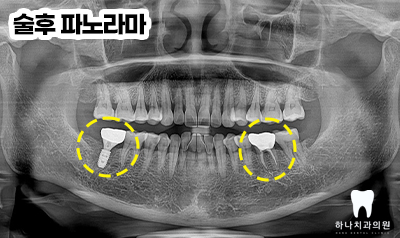

양쪽 아래 어금니가 파절된 이유로

내원해 주셔서 두 치아의 진.단은

파절에 해당하지만 그 양상과

치료 방법이 달랐는데요.

오른쪽은 발치 후 임플란트 수복,

왼쪽은 신경치료 후 크라운 수복을

계획하였습니다.